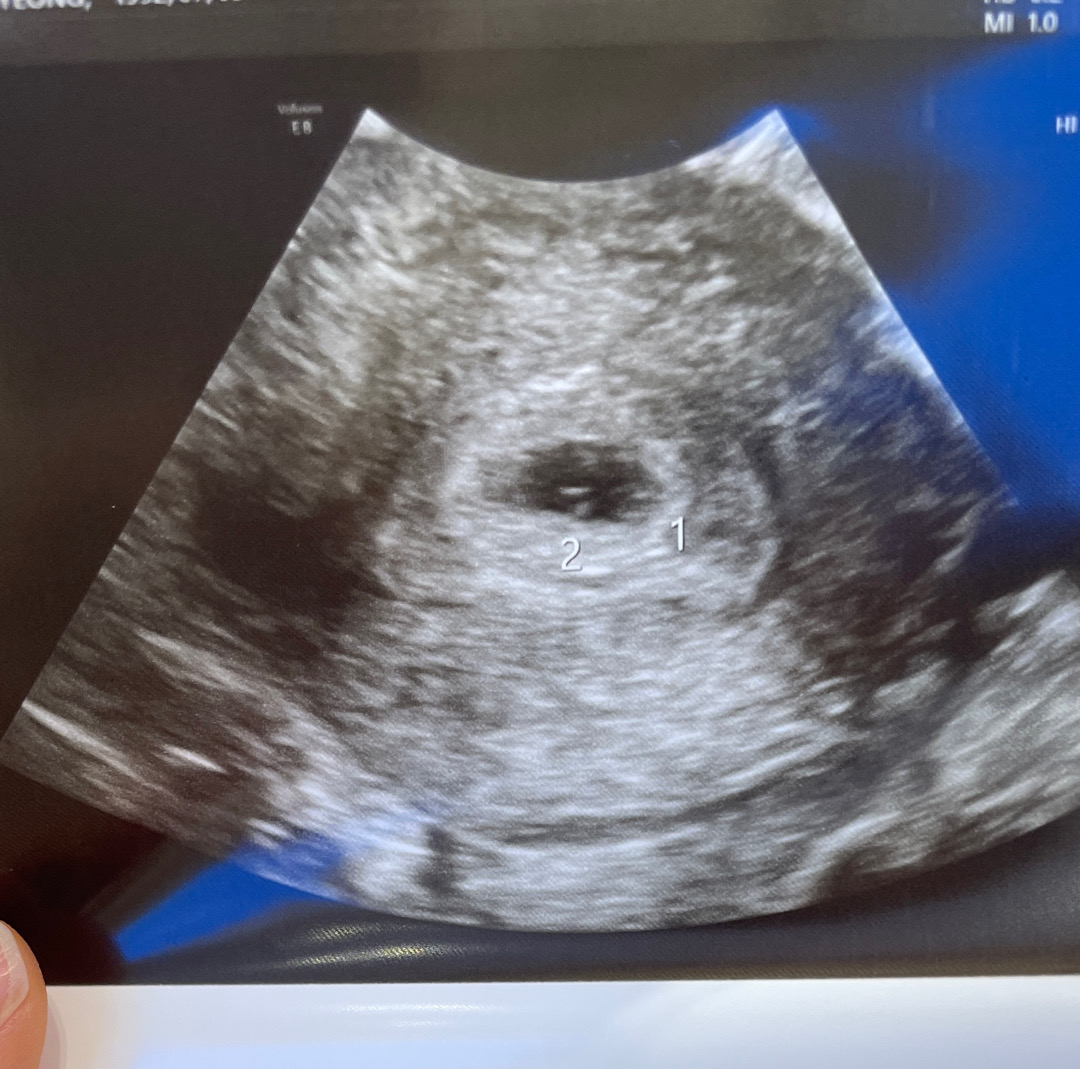

아기집 하나 난황 두개!!

첫 시험관으로 5일 눈사람 냉동배아 하나 (나이때문에 하나밖에 못한다고..) 이식해서 저번주 토요일 5주 2일차 첫 초음파를 봤는데 아기집 하나에 난황이 두개라 일란성 쌍둥이 말을 듣고 일단 지켜보자고 하시는데 예후가 너무 안좋은 글들만 가득하네요 ㅠㅠ 아기집 하나에 두명이 크는것 자체가 힘든거라고.. 사실 속으로 교수님 실수라도 하나 더 넣어주세요 .. 라고 간절히 바랬는데 ㅋㅋㅋㅋ 아 ㅠㅠ 저처럼 난황이 두개인 엄마들 어디 없나유 ㅠㅠㅠㅠㅠ